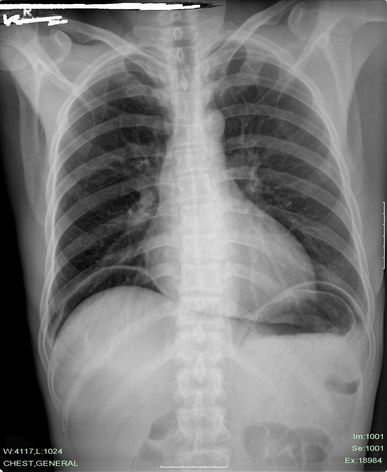

以下是引用老爱克斯新网客在2010-5-7 20:13:00的发言:[br]是真性气腹毫无疑问。不知患者性别,看胸片好像是男性,是否近期做过手术?或腹穿检查?了解病史。如果是女性,妇科的内诊检查,阴道冲洗,子宫输卵管造影术后等都可以出现真性气腹。详细了解病史必不可少。理论上讲还有肠气囊肿破裂,实际没见过。只要临床没有症状就不能轻易诊断消化道穿孔。